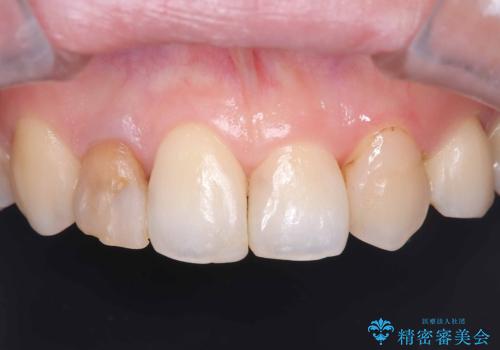

- 銀歯2本の下が虫歯になっていたので、フルジルコニアクラウンとセラミックインレーで治療を行いました。

適合が良い被せ物を入れるために、歯の境としっかり合わせた仮歯を入れ、歯茎の状態を良くしてからシリコンで型取りをしています。